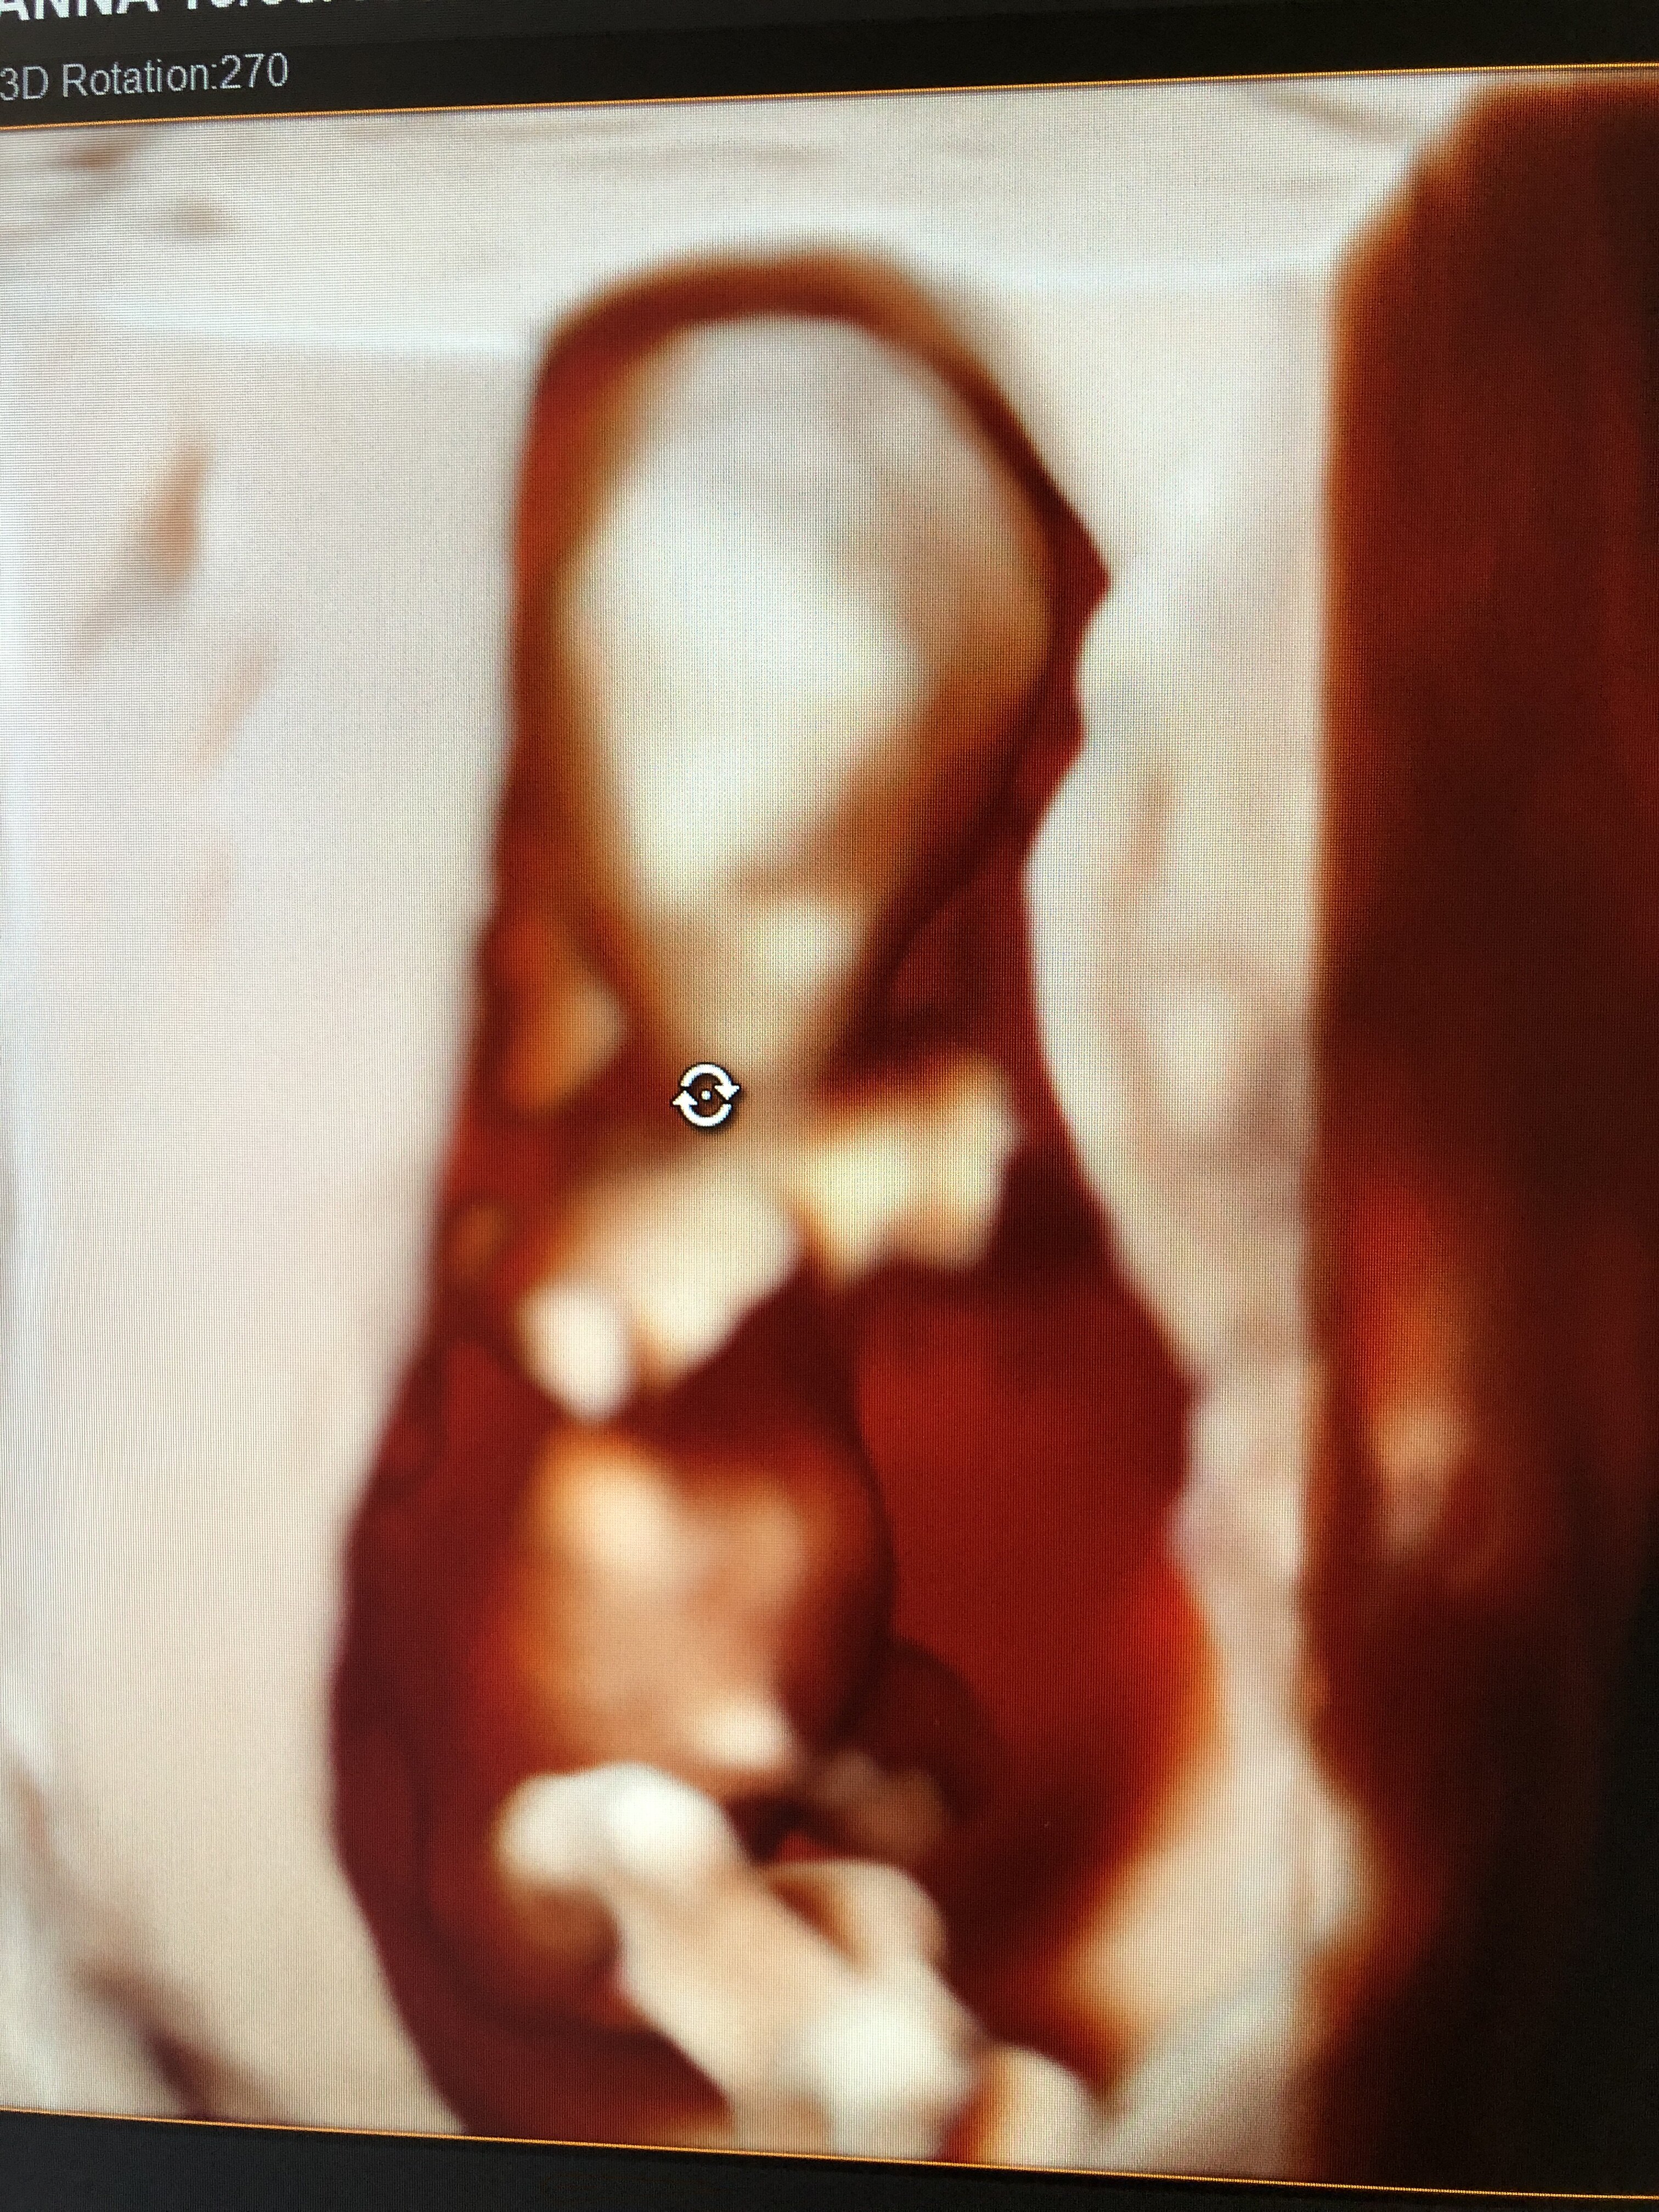

dziś miałam drugie prenatalne takie prywatne i wszystko idealnie. Po poniedziałkowym krwotoku ani śladu i wszystko pieknie. Dzidziuś się ustawiał dobrze :)

czekam na wyniki nifty ale padły nawet podejrzenia co do płci :)

No widzisz 💗 niema tego złego co by na dobre nie wyszło. Dzidziuś piękny! Jakie miałaś odstępy między tymi dwoma prenatalnymi i co tam się pokazało 👶🏼